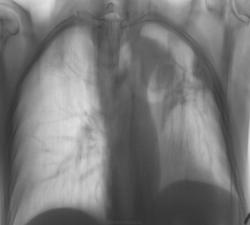

Картина серьёзная. Срединная тень смещена влево за счёт ателектазирования левого лёгкого. Имеется полость слева, шаровидное образование и изменение корня, который подтянут кверху. Справа туберкулома. Неужели фиброзно-кавернозный прижился с чем-то серьёзным?

Шаровидное образование слева - это ателектаз верхней доли, отсюда и подтягивание корня. Особо раскидывать мозги о причинах - не стоит. Может выйдет какой-то цирроз?, но думаю больше центральный рак.

Почему пишите ателектаз верхней доли, когда когда просветы бронхов прослеживаются? Если только - фиброателектаз, но это уже не центральный рак. "шаровидное образование слева" - элементы срединной тени смешенные влево (аорта). Субплевральо в верхнем отделе була. Что за тень прилежащая к плевре на уровне 3го ребра? Если пациент наблюдается, есть предыдущие снимки, была - фиброз, плевральные наложения; Появилась - онкология (?), должна быть боль в грудной клетке. Лежащее рядом ребро не изменено.

"Появилась онкология", или мицетома?